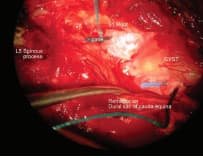

There was a large cyst at S1 and S2 communicating with the main dural sac via a narrow neck. The pressure in the cyst changes with filling of the cyst. Sacral nerves travel through the neck of the cyst to exist the sacral canal. As such, we decided on simple decompression of the S1 root and a laminectomy and not excision of the cyst which will require the sacrifice of sacral nerves passing through the neck and cyst.

PROGRESS: